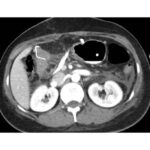

Tomografía de abdomen y pelvis con cte ev: del 13/10/2023.

Complicaciones posquirúrgicas

Tomografía de abdomen con cte ev: del 20/10/2023.

Tomografía de abdomen con cte ev: del 26/10/2023.